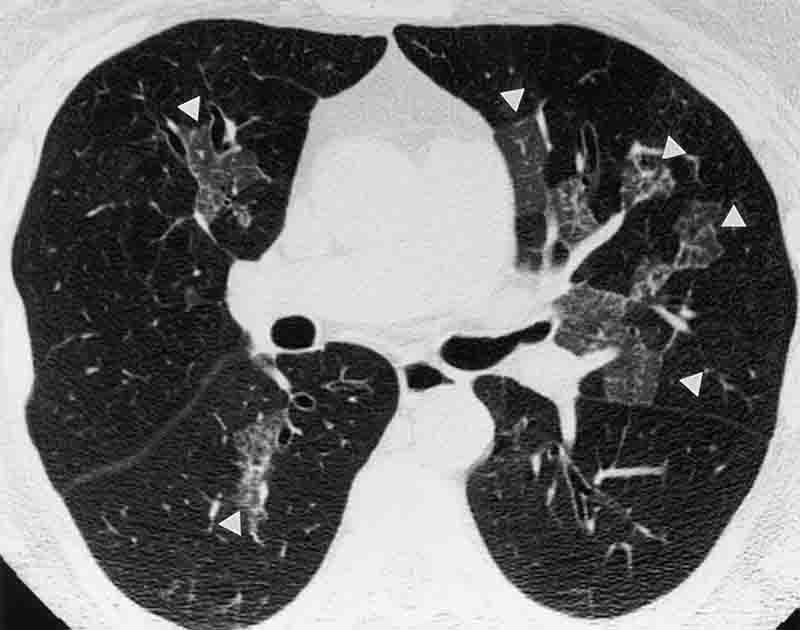

Normalized vasculature

โ Complex vasculature

In retrospective studies, tumors with more normalized vascular architecture (e.g., organized, more linear patterns) have been associated with more favorable outcomes to some standard therapies (e.g., immune checkpoint inhibitors). By contrast, tumors with more complex vascular architecture (e.g., twisted, disorganized patterns) have been associated with less favorable outcomes and lower responsiveness in some settings.